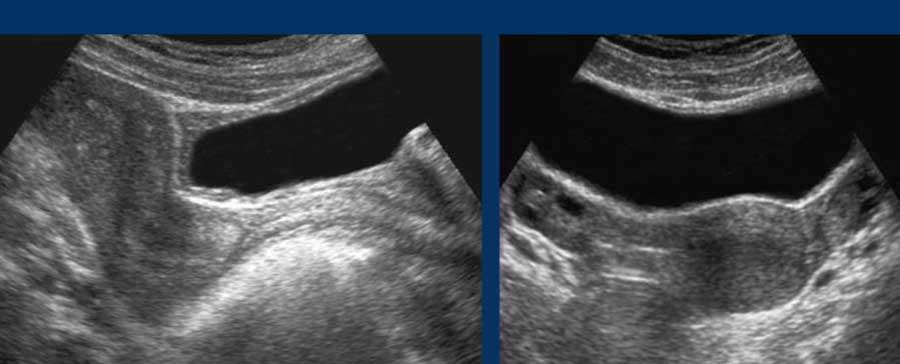

Hình ảnh siêu âm “xử lý quá mức”

Hình ảnh siêu âm đã qua xử lý: khử nhiễu đốm (speckle-noise-reduction)

- Ưu điểm: đường viền phản xạ sắc nét hơn, nang và mạch máu không có âm vang (anechoic), hình ảnh “mịn hơn”

- Nhược điểm: tạo ra các ranh giới và phản xạ không thực, độ phân giải hình ảnh thấp hơn

- Sử dụng hết sức thận trọng, vì các xảo ảnh gây nhầm lẫn có thể lấn át những ưu điểm của nó

Hãy so sánh hình ảnh siêu âm gốc (bên trái) của vùng tụy với hình ảnh siêu âm đã qua xử lý mạnh (bên phải).

Trong các hình ảnh xử lý quá mức này, các mạch máu có đường viền sắc nét hơn với lòng mạch hoàn toàn không có âm vang.

Tuy nhiên, các phản xạ và đường viền không thực cũng bị “tạo ra”.

Lưu ý các phản xạ sáng bất thường ở vùng phía sau đuôi tụy (hình trên bên phải) và đường viền kỳ lạ của dạ dày cùng dây chằng liềm (hình dưới bên phải).